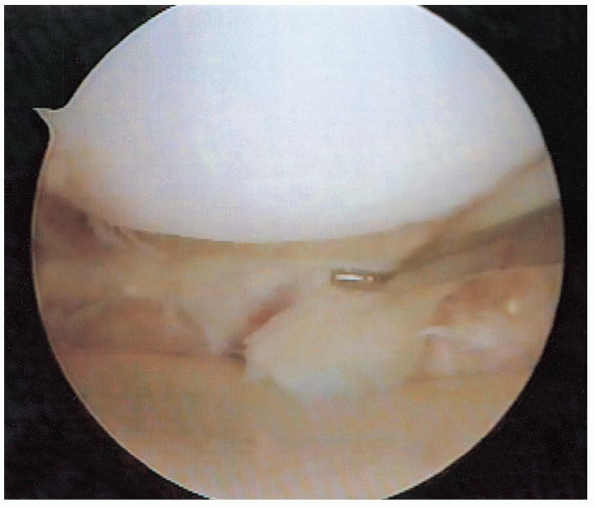

This can prevent inadvertent damage. The lens is then rotated to allow visualization of the anterior horn, body, and posterior horn of the medial meniscus (Figs. 25-14 and 25-15). Under direct visualization, a probe is used to manually palpate the superior and inferior surface of the meniscal tissue.

FIGURE 25-14. Visualization of the posterior horn of the medial meniscus, demonstrating a tear.